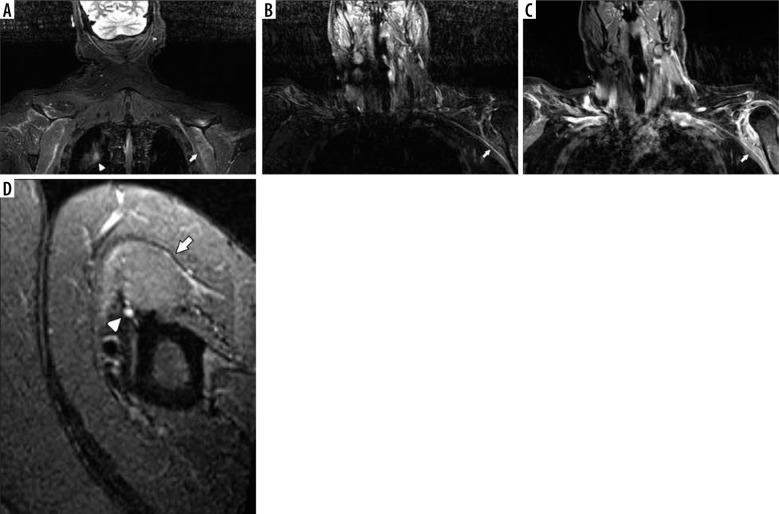

In this case series, we describe the magnetic resonance neurography (MRN) findings in 3 critically ill patients who presented with new onset of peripheral neuropathies in the extremities, and we discuss possible common mechanisms of nerve injury, including the role of position-related nerve injury.

MRN can be useful in identifying and localizing peripheral nerve abnormalities in the extremities of COVID-19 patients, and patients who are placed in the prone position during ventilation may be more susceptible to these injuries.